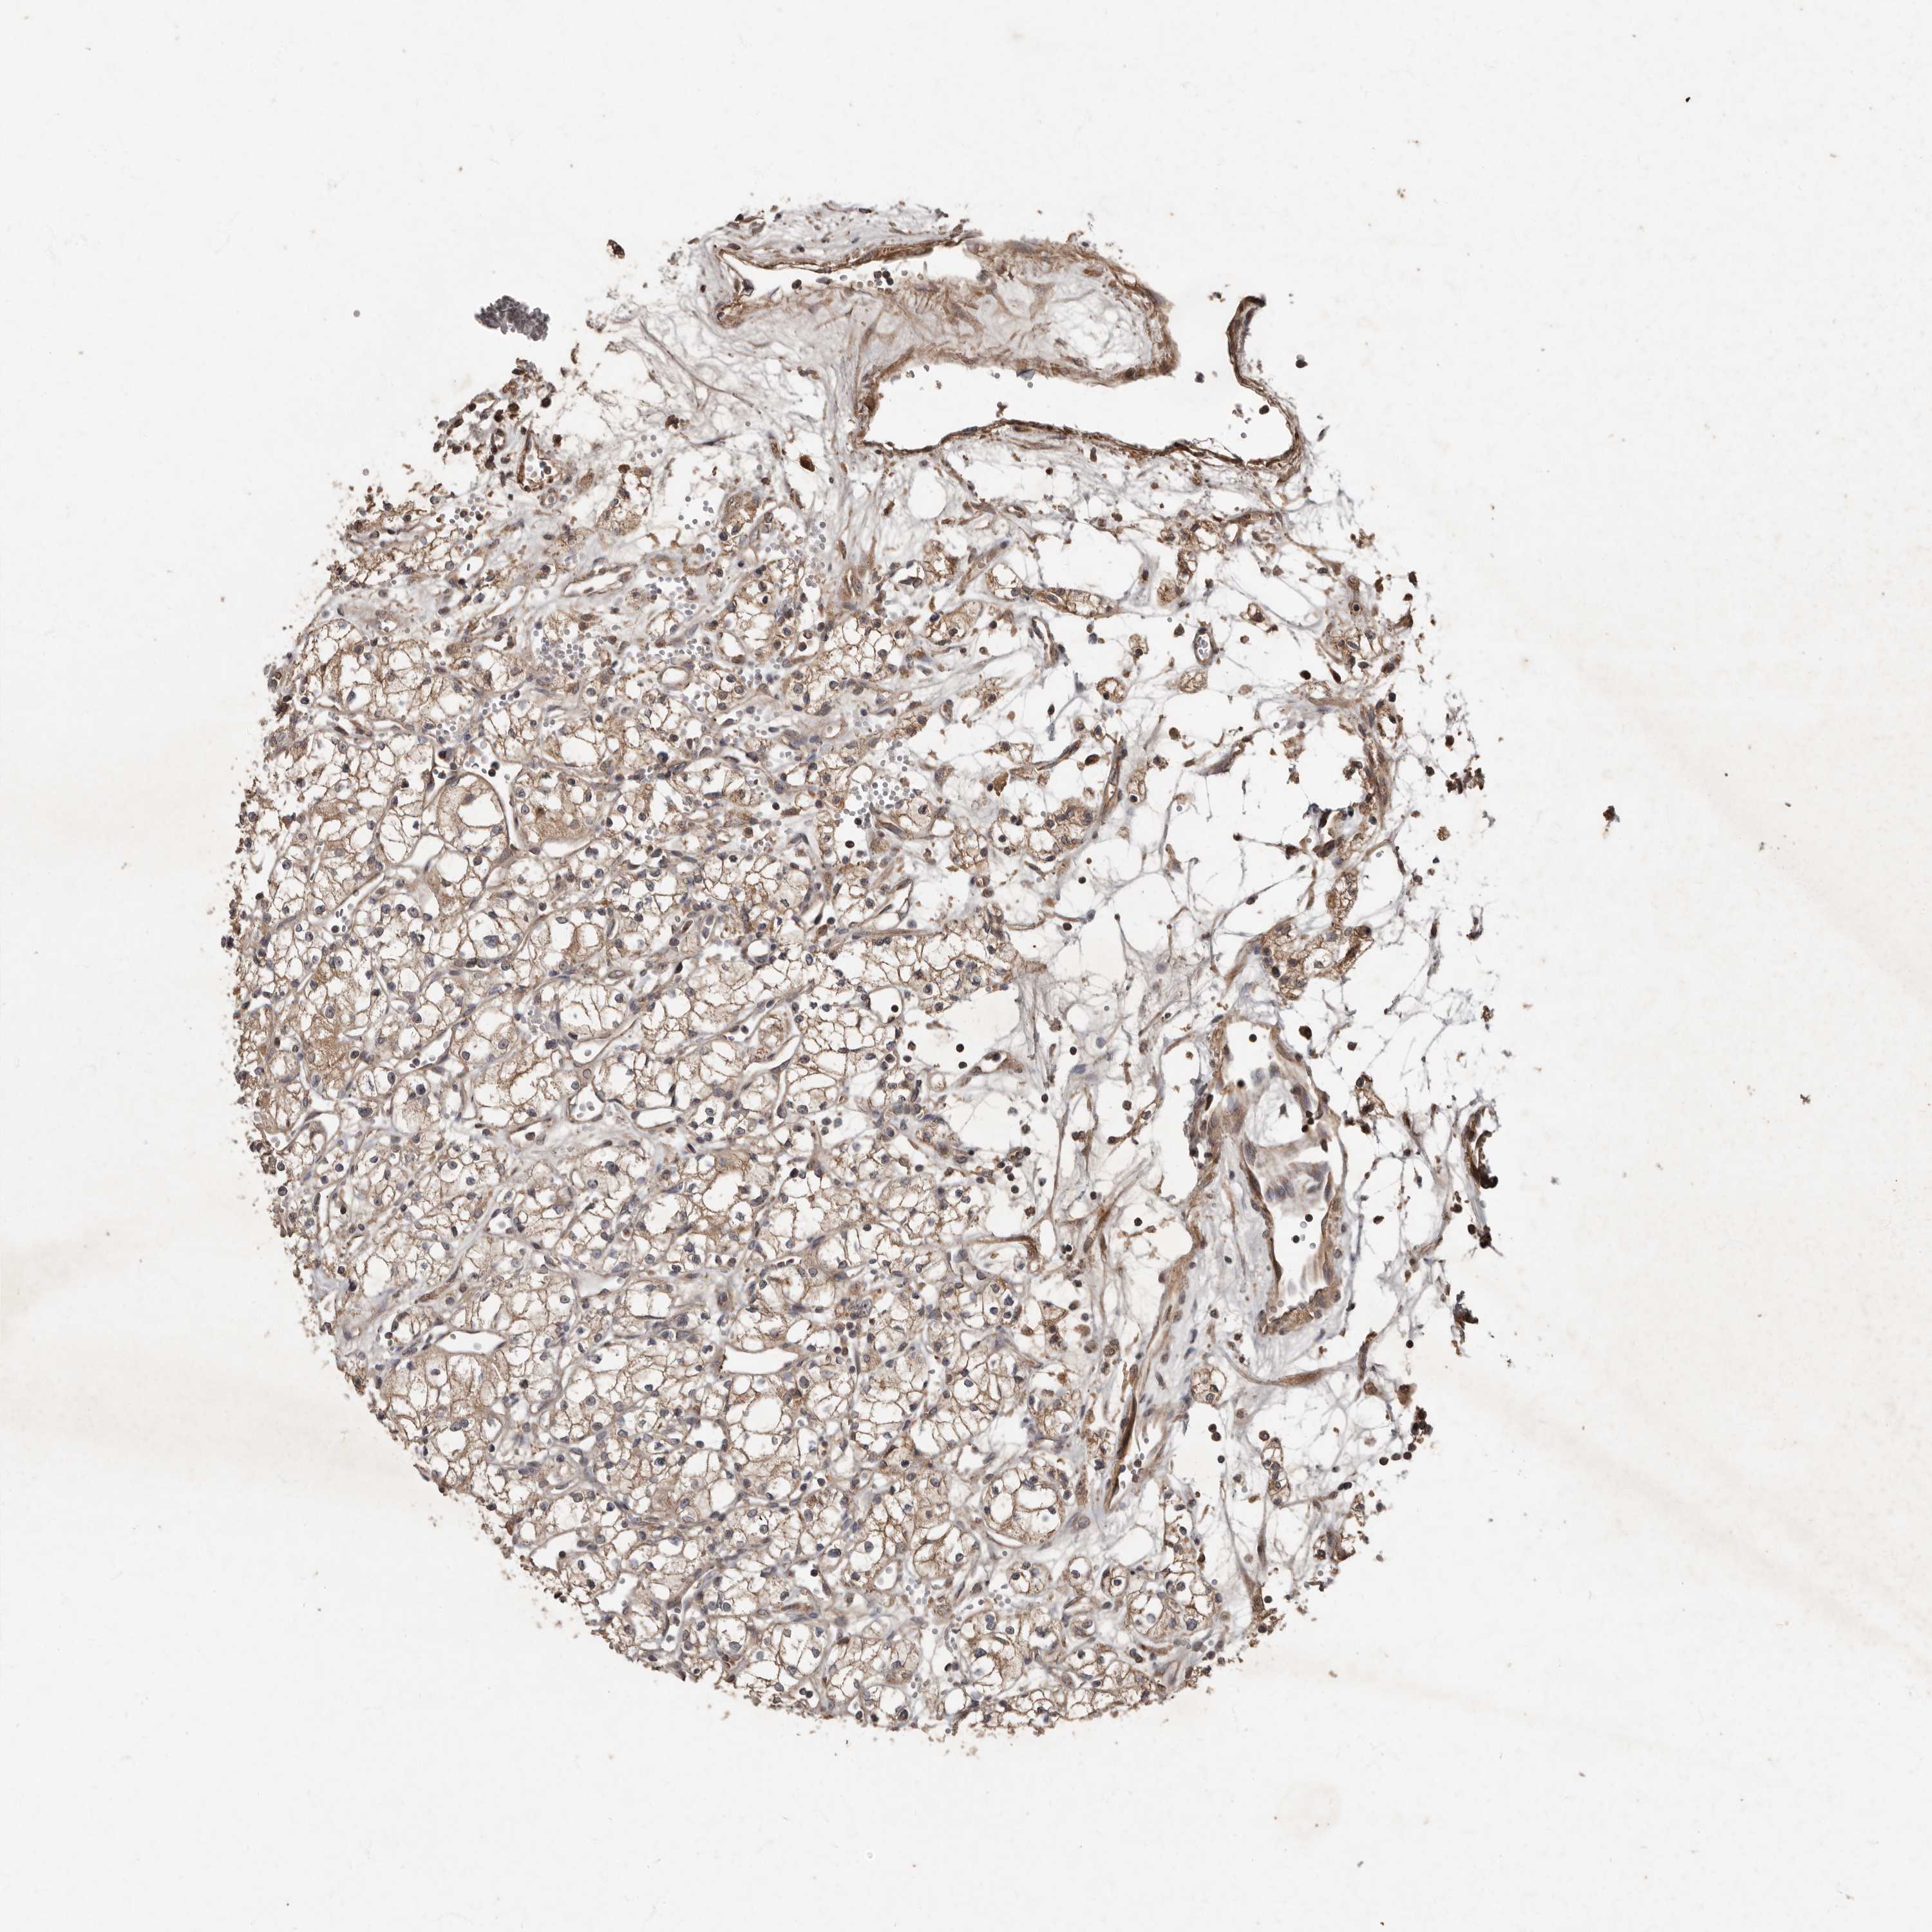

CANCER RENAL CANCER Show tissue menu

KICH TCGA KIRC TCGA KIRC VALIDATION KIRP TCGA PROTEIN RCC CPTAC PROTEIN EXPRESSION